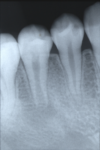

先日、小学校高学年の女の子が、歯が痛いと言って来院されました。お口の中をみると右下5番目の歯から出血がありました。レントゲン撮影など詳しい検査の結果、中心結節という歯の上の面の突起が折れて、歯の中の神経のお部屋が少し見えて出血していることが分りました。また、レントゲン写真から、この歯はまだ根っこが作られている途中で根っこの先が開いている状態の歯でした。このように根っこが成長している途中の歯を根未完成歯と言います。

実は、この根未完成歯は治療をするのが非常に難しく、根の先だけでなく神経のお部屋の内側の象牙質と呼ばれる歯の成長も行われている途中の歯なのです。従って、根っこの成長が終わった歯と比べてこの歯は薄く、歯が割れるリスクが高いのです。根の成長を止めずに治療することができれば理想的であると言われています。

・成長途中の永久歯(生え変わる大人の歯)にみられるもので、根っこの先はラッパ状に広がっている

・根っこの先の歯は非常に薄く脆い

・根っこの先には歯をつくる作用をもつ細胞がたくさんある